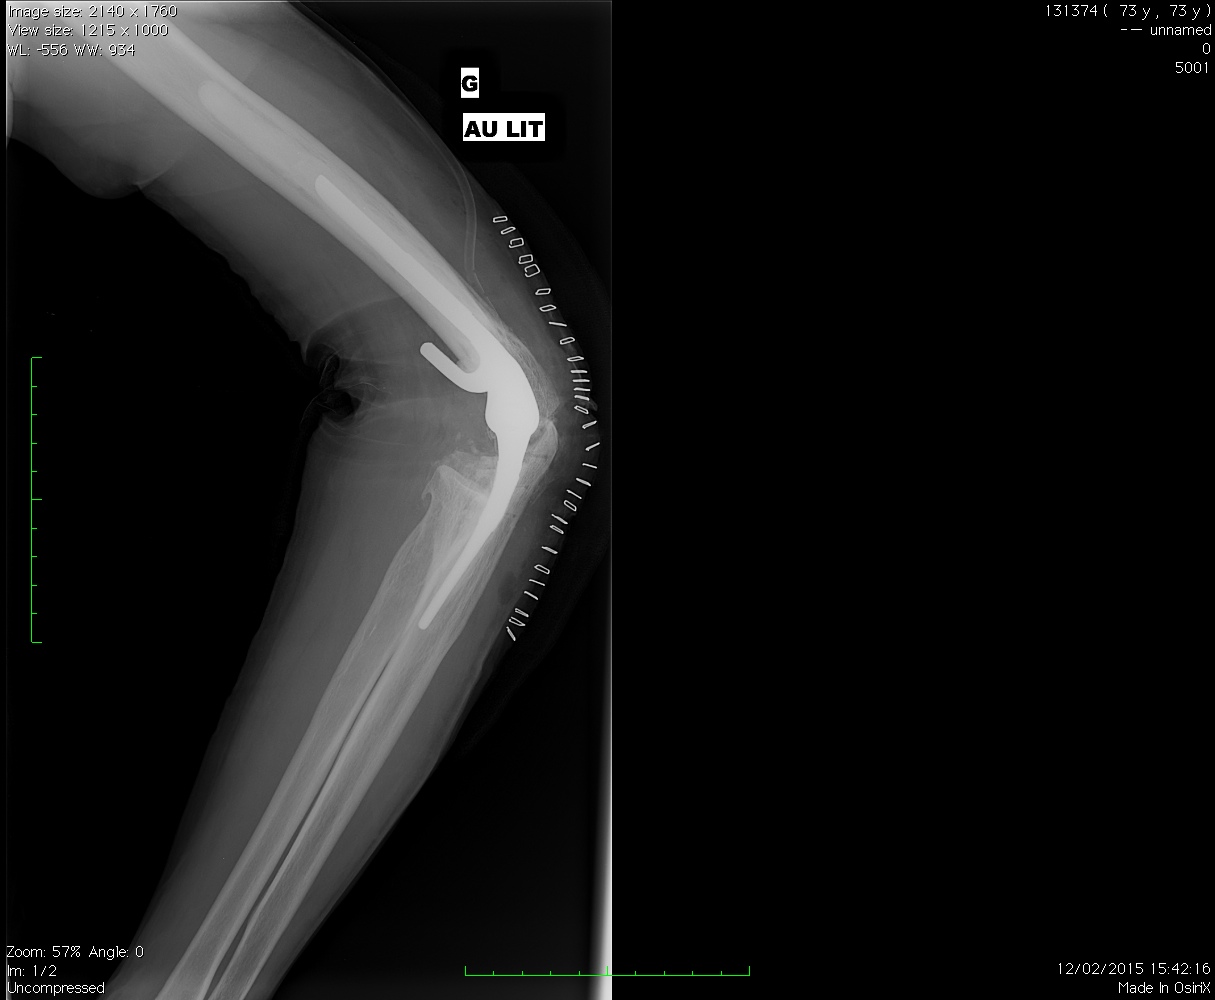

Voici un exemple de l’aspect radiologique une fois la prothèse mise en place.

La prothèse est constituée d’une tige métallique introduite dans l’humérus et une autre dans le cubitus, les deux étant relié par une charnière articulée.

Il faut donc remplacer les surfaces articulaires et reconstruire l’articulation avec une prothèse totale de coude qui va donc remplacer essentiellement l’articulation huméro cubitale (entre l’humérus et le cubitus)